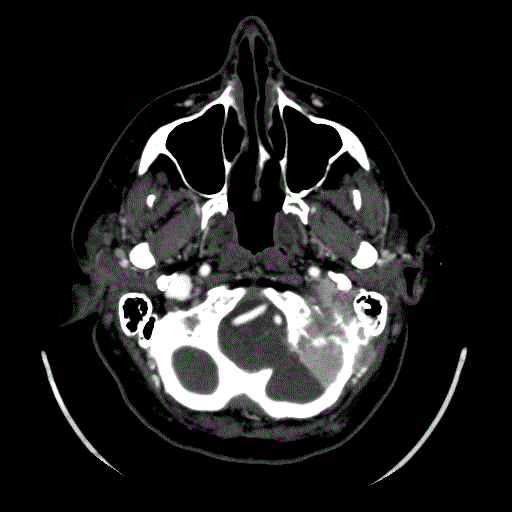

Les paragangliomes

Ce sont des tumeurs rares qui se forment près de l’artère carotide, la veine jugulaire ou le long des voies nerveuses de la tête et du cou. Certains paragangliomes sécrètent des catécholamines – des hormones produites habituellement par les glandes surrénales – appelée adrénaline et noradrénaline. La libération de ces catécholamines dans le sang peut provoquer des symptômes tels que hypertension artérielle, maux de tête, transpiration, rythme cardiaque rapide ou irrégulier, pâleur et tremblements.

Les paragngliommes peuvent être de deux types : sporadiques, ou familliaux. Dans ce dernier cas ils touchent plusieurs personnes de la même famille, surviennent chez des patients plus jeunes et sont souvent multiples.

Le traitement consiste habituellement en l’exérèse complète de la tumeur par le chirurgien ORL.

Localisation d’un paragangliome du foramen jugulaire (d’après Jackler, ATLAS OF SKULL BASE SURGERY & NEUROTOLOGY. Thieme. ©2009 )

Plusieurs forment cliniques existent :

Les tumeurs du corpuscule carotidien, qui sont une entité rare et à croissance lente . La symptomatologie est celle d’une masse cervicale pulsatile. Les tumeurs du corps carotidien peuvent être traités par chirurgie le plus souvent ou la radiothérapie, mais moins souvent.

Les tumeurs du Glomus vagal sont des excroissances qui proviennent dans les corps glomiques près du nerf vague (ou X), le plus long des nerfs crâniens. Les symptômes comprennent la paralysie des cordes vocales, des acouphène pulsatiles ou des troubles de la déglutition.

En règle générale, la chirurgie par un ORL est recommandé et permet d’enlever la tumeur. Si la tumeur se prolonge dans le cerveau, neurochirurgien aide à la résection de la tumeur.

Les tumeurs Glomus jugulaire sont rares. Il s’agit de tumeurs à croissance lente qui commencent dans l’os temporal (os de l’oreille) et se propagent à travers l’oreille. Les symptômes les plus courants sont des acouphènes pulsatiles ou une perte auditive. La tumeur peut se propager par la suite vers le cerveau, le nerf facial et l’oreille interne, affectant l’audition et de l’équilibre.

Ces tumeurs sont traitées chirurgicalement par les membres de l’équipe ORL ou par radiochirurgie stéréotaxique si elles sont très petites.